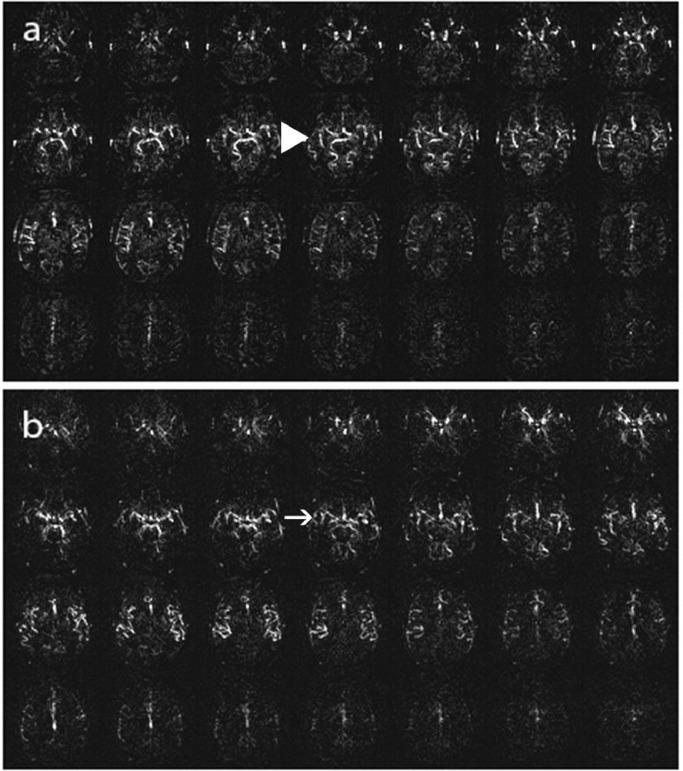

We employed a five-stage scale (0 being normal and 4 indicating the most severe perfusion decline) to assess 156 patients using a 3D pulsed ASL technique. Three radiologists independently reviewed the images, and inter-rater reliability of the visual rating scale was evaluated.

The ASL stages showed a consistent distribution among the patients. The inter-rater reliability among the three radiologists, as measured by the Intraclass Correlation Coefficient (ICC), was 0.982.